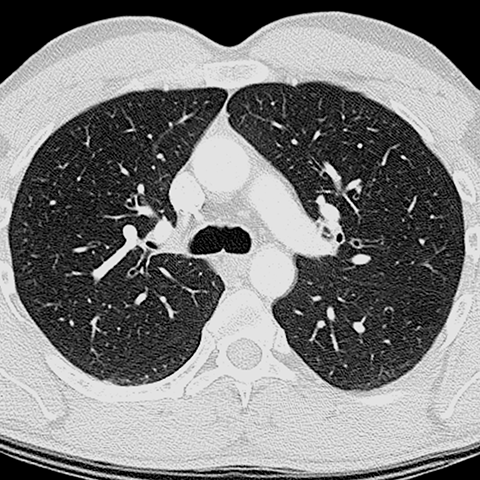

HRCT of Previous Image [6 of 8]